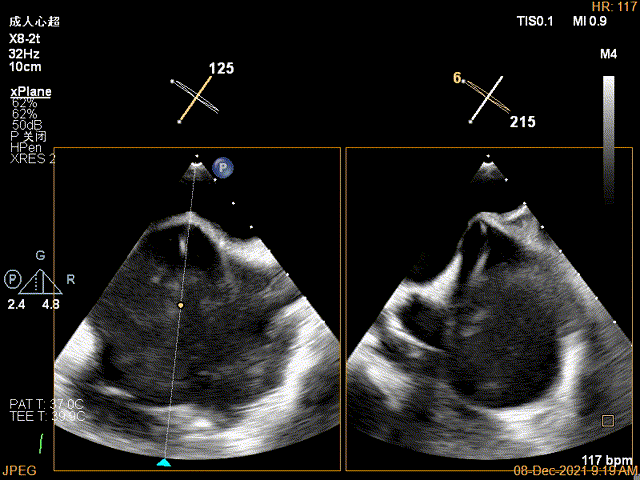

3D-VIEW验证结果

3D-Color-view验证残余分流位于外侧